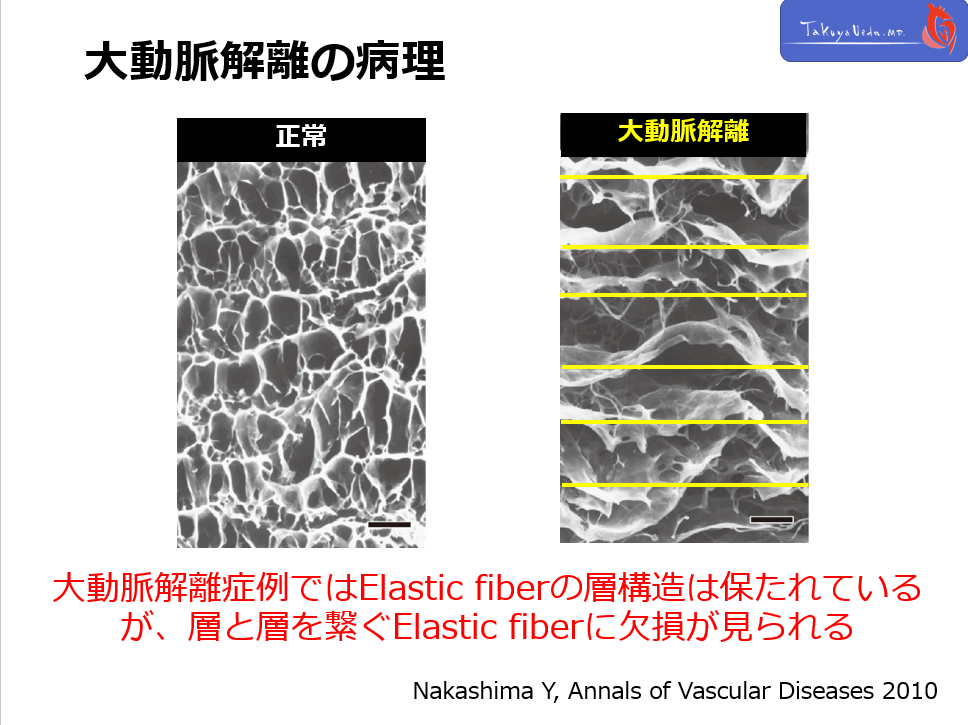

Pathogenesis of aortic dissection is loss of tight connection of elastic lamina. In AoD patients, 3D tight relationship of elastic fibers has gone.

Fig. 2 Histological appearance of the human aortic media. a b �a: Normal subject.�b: Aortic

dissection patient. Elastic fibers appear dark brown (Elastica van Gieson stain). Upper, intimal side. Lower, adventitial side. Scale bar = 50 μm. Elastic fibers appear dark brown (Elastica van Gieson stain).